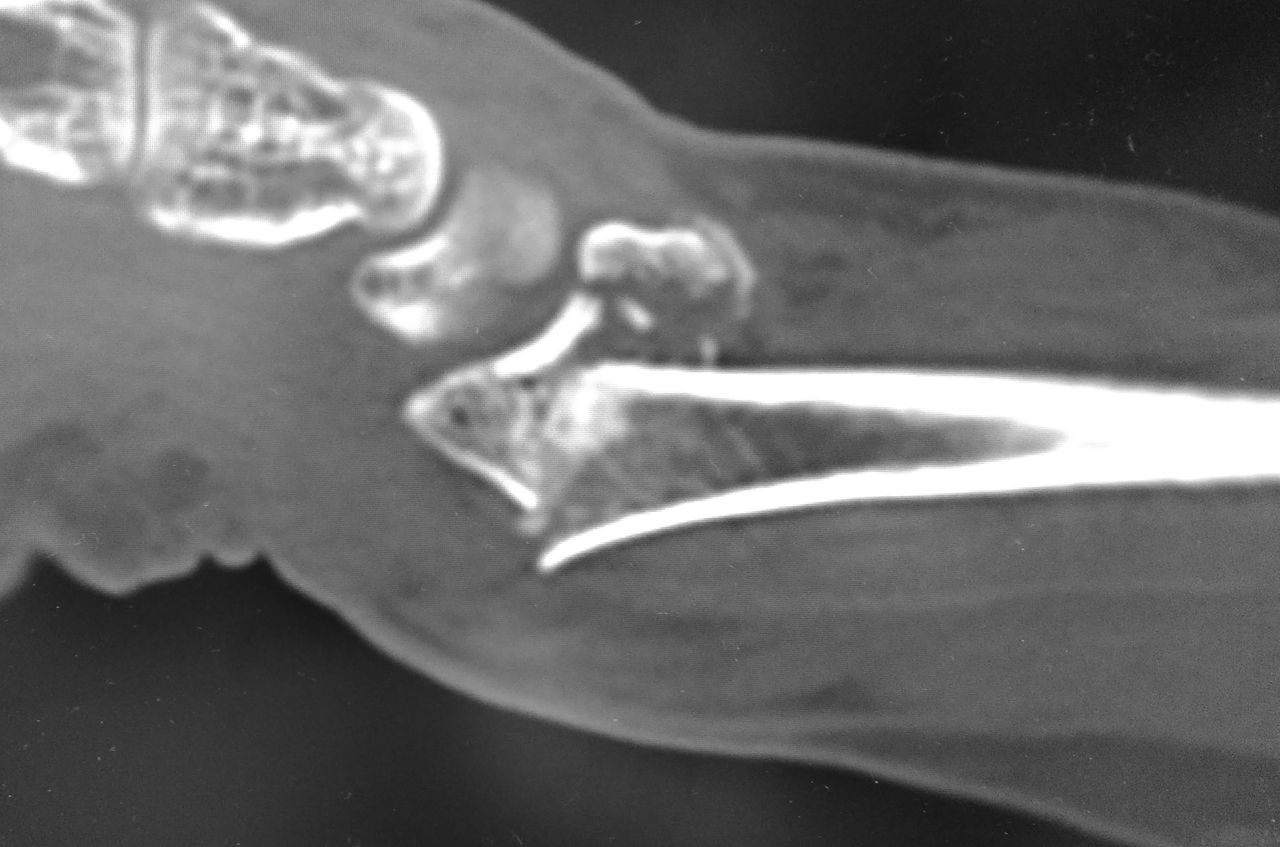

下の画像のように、かなり厳しい転位のある症例でした。

今回は、末梢側骨片の海綿骨が圧壊しており、整復するとかなりの骨欠損が生じる可能性があります。このような症例では、骨移植するべきなのでしょうか?

今回の経験から、橈骨末梢側骨片の皮質骨まで粉砕しているため開窓しなくても骨移植できる場合を除いて、基本的には骨移植しない派に立ち位置を定めました。